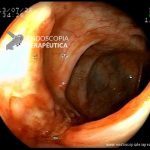

- Doença de Crohn em remissão – cicatriz